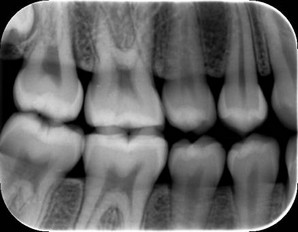

PSP plates are especially advantageous for bitewing imaging. Plate thinness and an active area that encompasses the entire plate allow the practitioner to easily capture the distal of the canine in a premolar bitewing (Figure 3). For ease of use, patient comfort and low cost of sensor replacement makes a PSP system a logical choice when planning for digital imaging in a dental practice.